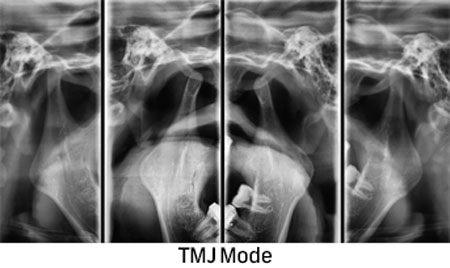

Преку нашите истражувачки активности, нашиот тим е запознаен со најновите научни наоди и може да ги исполни највисоките технолошки и професионални очекувања. За прегледи и проценки, имаме широк спектар на опции. Користиме различни методи за сликање, како што се проекциона радиографија, томографија и компјутерска томографија.

Kористиме најнова технологија за да овозможиме прецизен третман за нашите пациенти преку методи на снимање.